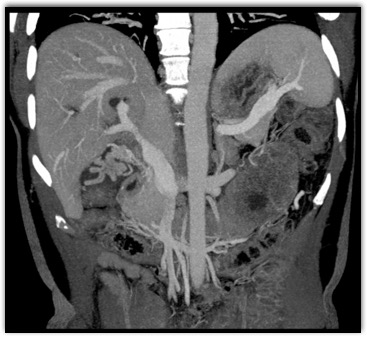

The least likely diagnosis in this case is?

lymphoma

cholangiocarcinoma

acute hepatitis

hepatoma